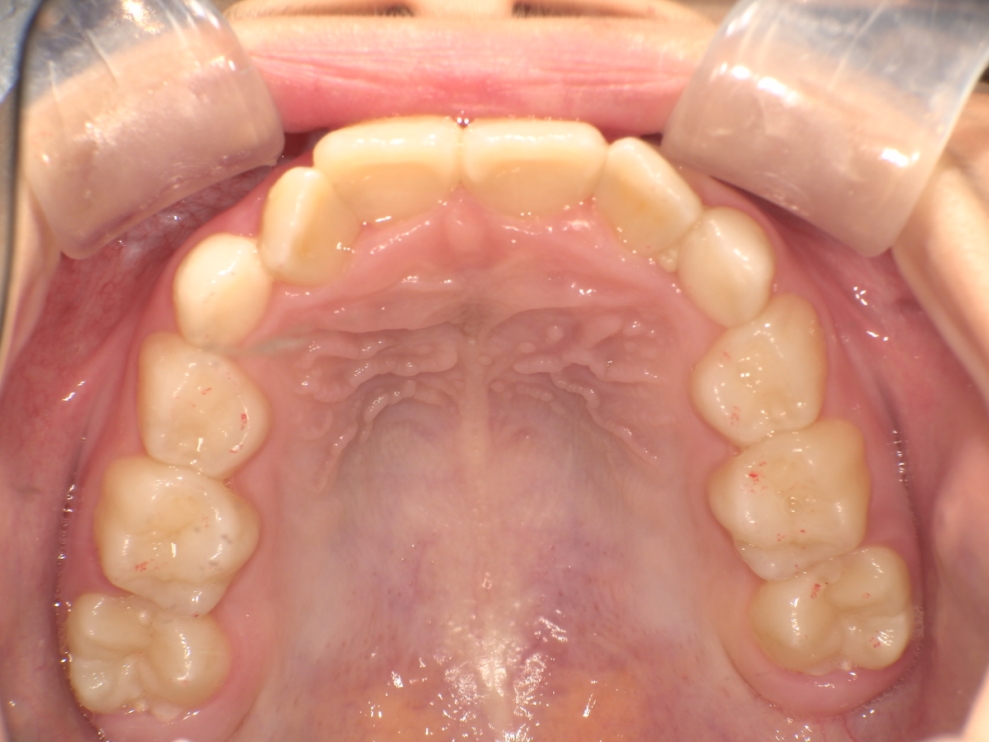

AFTER

治療は、マウスピース矯正インビザライン・ファーストにて矯正治療を行い、成長を活かしながら歯列と噛み合わせを整えていきました。治療期間は1年2ヶ月で、ガタつきと深い噛み合わせが改善し、将来を見据えた安定した歯列環境を整えることができました。

成長期だからこそ可能なアプローチで、早期に問題を改善できた症例です。